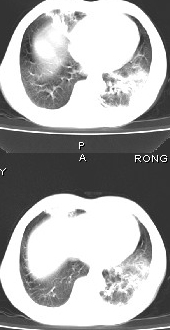

男68岁,反复发热、咳嗽,咯痰1月,曾有咯血史,双肺闻及呼吸音增粗。

左肺上叶尖后段及下叶多发实变阴影,内见支气管充气征,段以上支气管尚通畅,肺门区未见软组织肿块影,结合病人有反复发热病史,首先考虑感染性病变(干酪性肺炎不能排除),建议抗炎治疗后复查或结合纤支镜检查。

左肺上叶尖段及下叶干酪性肺炎可能性大,建议结合临床相关检查.右肺中叶炎症.建议治疗后复查.

该患者在25天前外圆平片见右肺中上肺野大片状影,(治疗不祥,在反复问病史后患者告诉;近一月住在新房内,搞装修),我认为首先考虑是感染,而且过敏性肺炎可能性大。